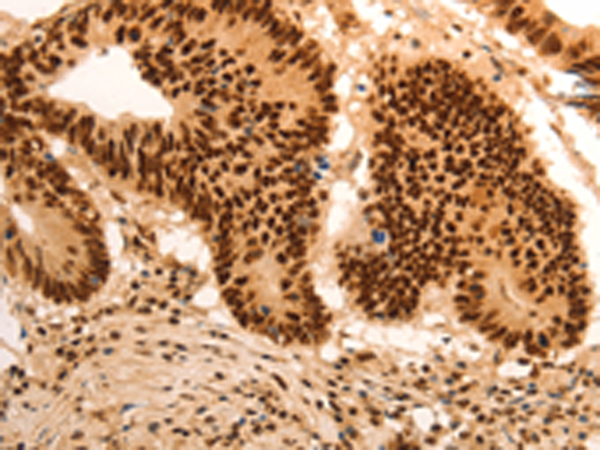

Atypical E2F transcription factor that participates to various processes such as angiogenesis, polyploidization of specialized cells and DNA damage response. It plays a key role in polyploidization of cells in placenta and liver by regulating the endocycle, probably by repressing genes promoting cytokinesis and antagonizing action of classical E2F proteins (E2F1, E2F2 and/or E2F3). |

ELISA, IHC |

IHC positive control: |

Human colon cancer and human gastric cancer |

IHC Recommend dilution: |

50-200 |